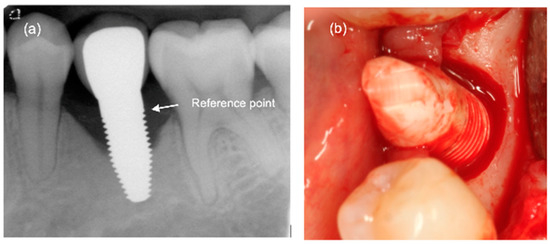

Follow-ups (Appendix A and Appendix B) were performed after 1, 3, and 5 years, including assessment of the papilla index (PI) according to Jemt [24], the probing depth (PD), the clinical attachment loss (CAL), the modified bleeding index (mBI), and the modified plaque index (mPI); the two last indices were according to Mombelli et al. (1987) [25]. The patient reported outcome measurements (PROMs) “function, aesthetics and appearance, sense, speech, and self-esteem” were assessed using a visual analogue scale (VAS). This is a measurement tool for subjective characteristics which cannot be directly measured. The customised film holders were used to take standardised radiographs to monitor bone remodelling over time. For the measurement of bone remodelling over time, the radiographs were calibrated using the known width of the base of the abutment part of the ceramic implants. The lower edge of the implant abutment part was used as the reference point for the measurements (Figure 1a). An independent radiologist at the University of Gothenburg, Sweden, examined all radiographs. Implant success grading as proposed by Östman and co-workers [26] was slightly modified and defined as grade I for implants with no clinical and radiographic signs of pathology showing ≤ 2 mm bone resorption. Success grade II was assigned to implants with no clinical and radiographic signs of pathology and ≤3 mm bone resorption. At the follow-ups, patients were screened for biological complications and other adverse events as well.

Figure 1.

(a) Exemplary radiograph at the 5-year follow-up depicting a single-tooth implant with a distinct vertical defect at the mesial and distal aspect of the implant. The lower corner of the straight cylindrical implant part was used as reference point for bone level calculations. (b) Clinical situation of the same implant prior to removal.

3.3. Marginal Bone Remodelling

From implant insertion (II) to PI, the mean marginal bone loss was 1.13 mm and from II to the 1-year follow-up it was 1.31 mm. A bone loss of 1.45 mm between II and the 3-year follow-up and of 1.12 mm between II and the 5-year follow-up was found. The results indicate that there was a slight further increase in bone loss from the 1-year to the 3-year follow-up but a decrease in bone loss from the 3-year to the 5-year follow-up (Table 7). At the 5-year follow-up, at 11 of 41 eligible implants (27%), a marginal bone loss of more than 2 mm was detected. Of these 11 implants, 5 demonstrated more than 3 mm of bone loss. This resulted in a 73% success grade I and to 88% success grade II after 5 years [26]. An exemplary radiograph and clinical picture show the typical bone loss pattern (Figure 1). Regarding any influence or correlation of baseline parameters, the performed univariate analysis did not disclose any effect or correlation of these parameters onto the bone remodelling/loss from implant insertion to the 5-year follow-up (Table 8).